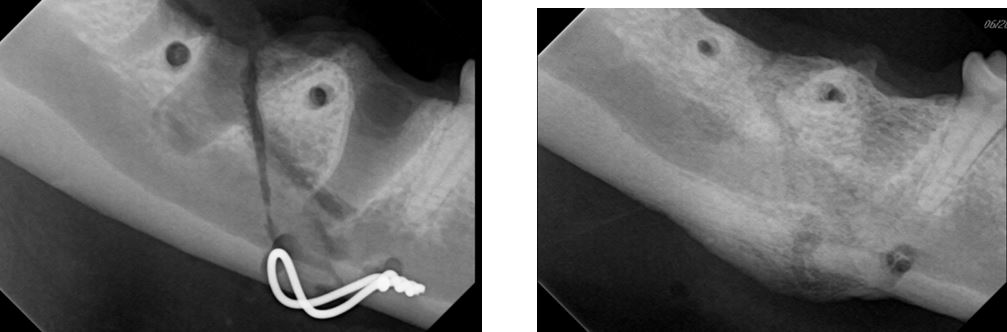

Figure 4 (A + B). Same patient as Figures 1, 2, and 3. Dental radiographs of mandibular fracture at the level of the mandibular first molar (409). The injury involves a fracture of the distal root of the tooth as well as a disruption of the bone at the apical region of the mesial root. There is a periodontal disease associated with the second molar (410) unrelated to the injury.

Figure 5 (A + B). Same patient as Figures 1, 2, 3, and 4. Figure A shows the intraoperative placement of an intraosseous wire. Pilot holes have been created for the dorsal wire, aiming for wire positioning that is approximately perpendicular to the fracture line. The ventral wire is in a “figure 8” on the ventral aspect of the mandible. Figure B is two months after fracture repair, and intraosseous wires are removed. Union between the bone segments is present, along with callus formation along the ventral mandible.